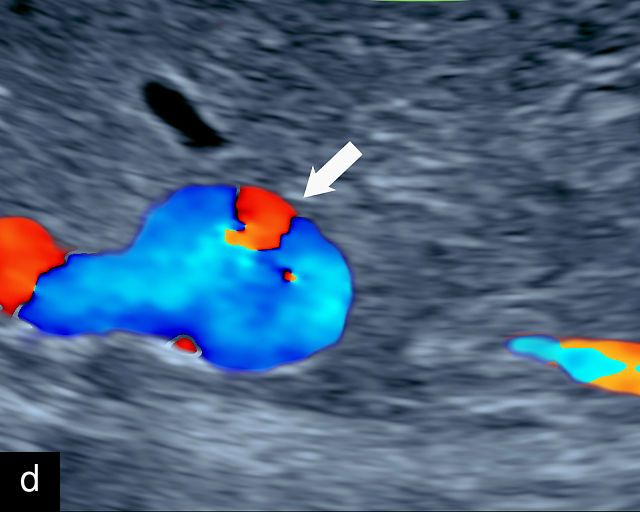

There are three types of vasa previa.30,262 In Type 1, the cord inserts into the membranes rather than the placenta. Unprotected vessels then traverse the membranes over the cervix to insert into the placenta (Figure 21a; Video 12). In Type 2, unprotected vessels running through the membranes over the cervix connect the main placental lobe with an accessory lobe (Figure 21b).263 In Type 3, there is generally a normal placental cord insertion, and unprotected vessels exit one placental edge, run through the membranes over the cervix and then boomerang to insert into the placental edge at another site (Figure 21c).25,28,29,264 Regardless of the type, all these expose the fetus to the same risks.

21